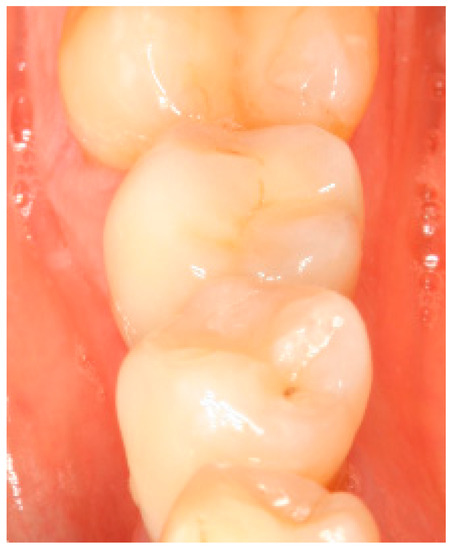

Situation after crwon cementation. Occlusal view.

Figure A1.

Clinical situation at the 1-year follow-up. Occlusal view.

Figure A4.

Clinical situation at the 3-year follow-up. Occlusal view.

Figure A7.

Clinical situation at the 5-year follow-up. Occlusal view.

Figure A10.